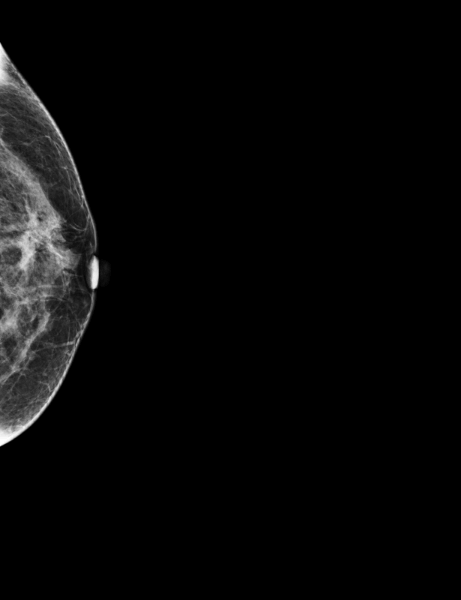

During the screening, two masses were found, one on the right breast (2cm DTN) and the other on the left breast (A1 cm DTN), categorized as suspicious.

The patient was called back for an ultrasound. The following biopsy performed showed lobular cancer infiltrating the left breast (two masses).

MammoScreen indicates one of the suspicious masses on the left breast in score 8 on tomosynthesis.